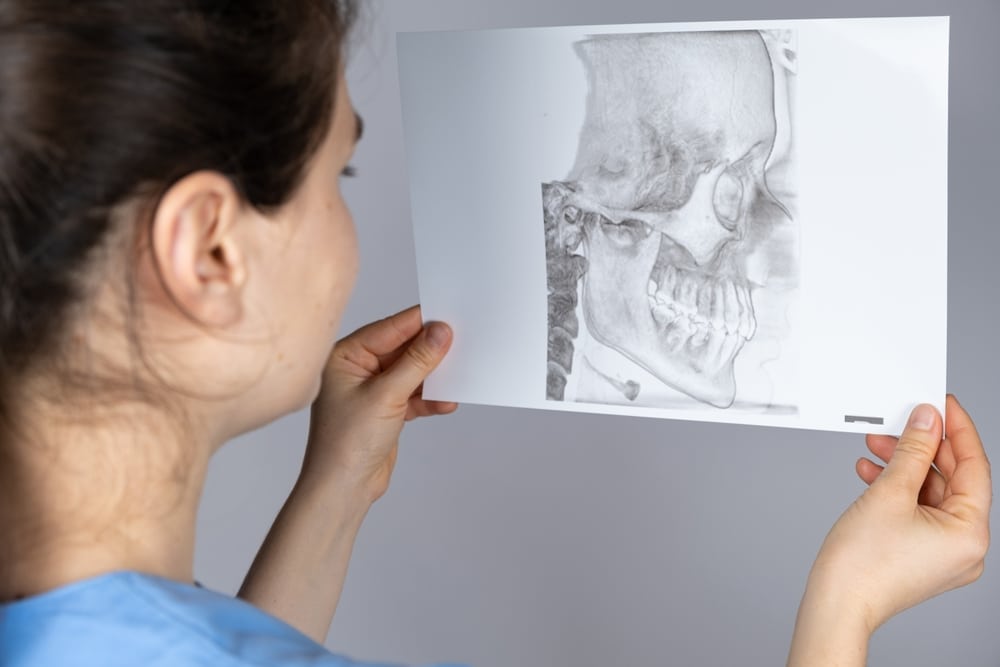

What Is The TMJ?

The temporomandibular joint (TMJ) is a small but vital joint that connects your jaw to your skull. It enables important functions like chewing, speaking, and yawning. Its complex structure relies on proper alignment and coordination to work smoothly and without discomfort. When this joint functions as it should, you can go about your day without thinking twice.- Location: Positioned on both sides of the face near the ears.

- Functionality: Acts as a hinge and sliding joint for smooth jaw movement.

- Importance: Supports essential activities such as eating, speaking, and breathing.

- Complexity: Requires coordination of bones, muscles, and ligaments.